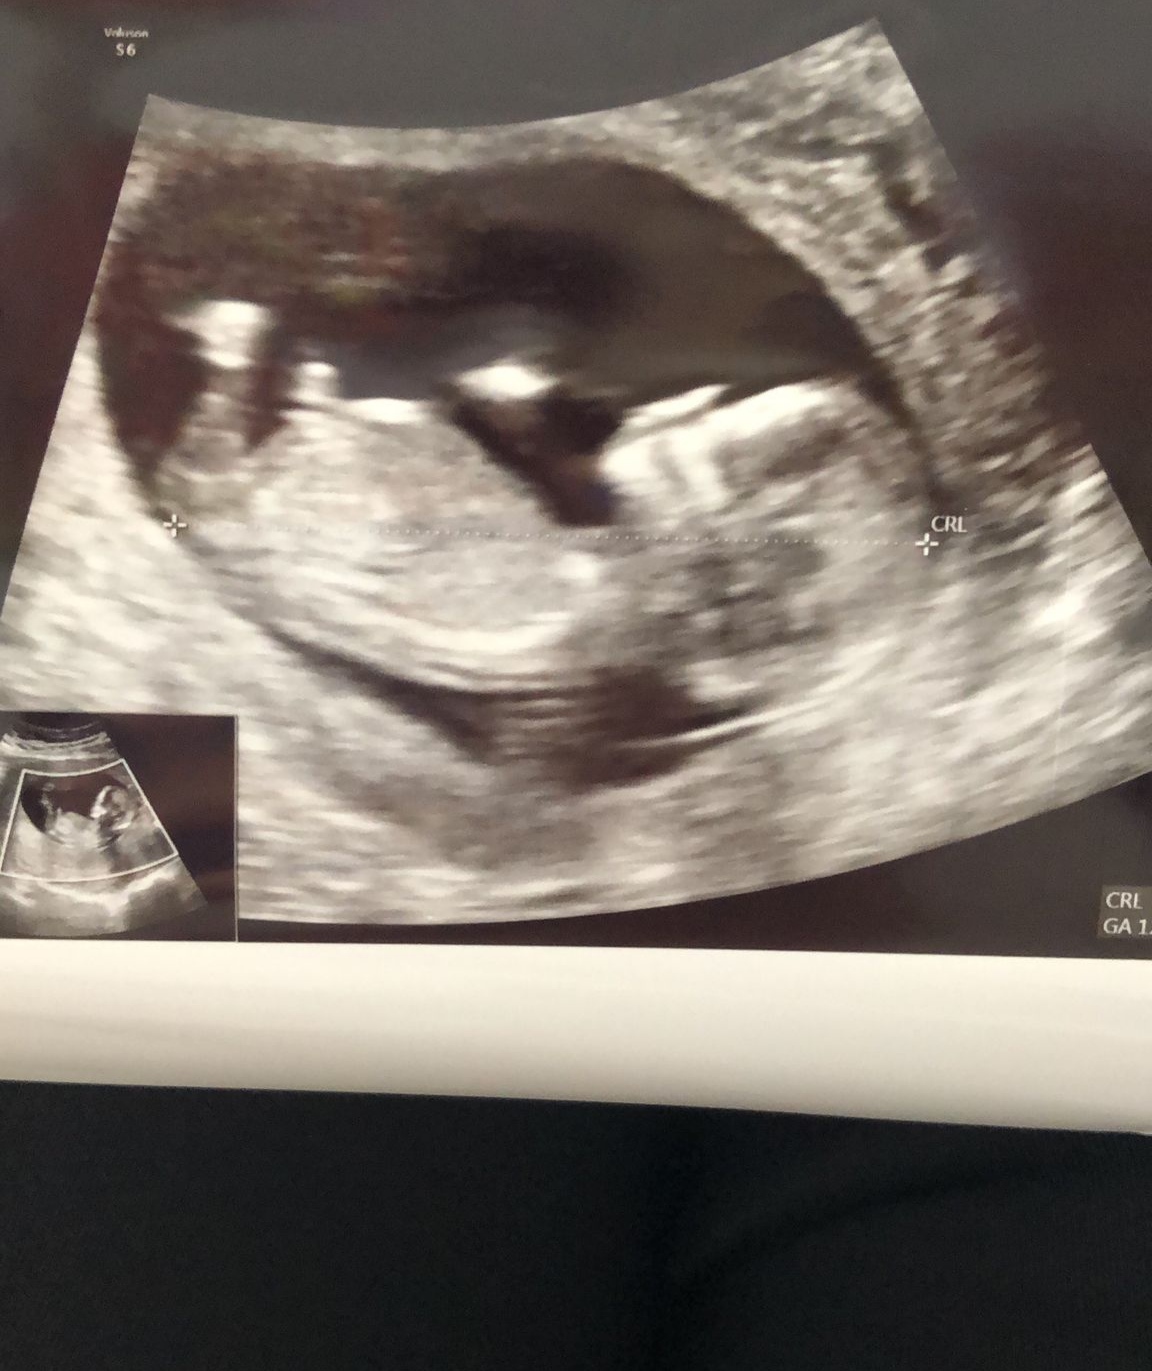

Baş şekli vücud şeklinden tahmininiz olurmu acaba teşekkürlerSelamlar Sevgili Nermin, Resmi baya inceledim ama görmemiz gereken genital tüberkülül görünmüyor dolayısı ile bir cinsiyet tahmini malesef yapamıyorum. Başka resim var ise yükleyin onlara da bakalım olur mu ?